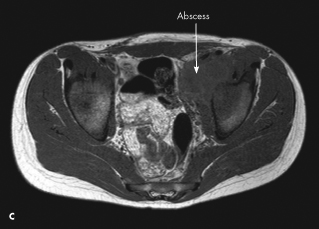

An MRI scan of the pelvis revealed osteomyelitis of the left acetabulum with infectious and inflammatory changes along the course of the iliopsoas muscle tracking superiorly (C). An iliopsoas abscess within the left pelvic region was also identified.